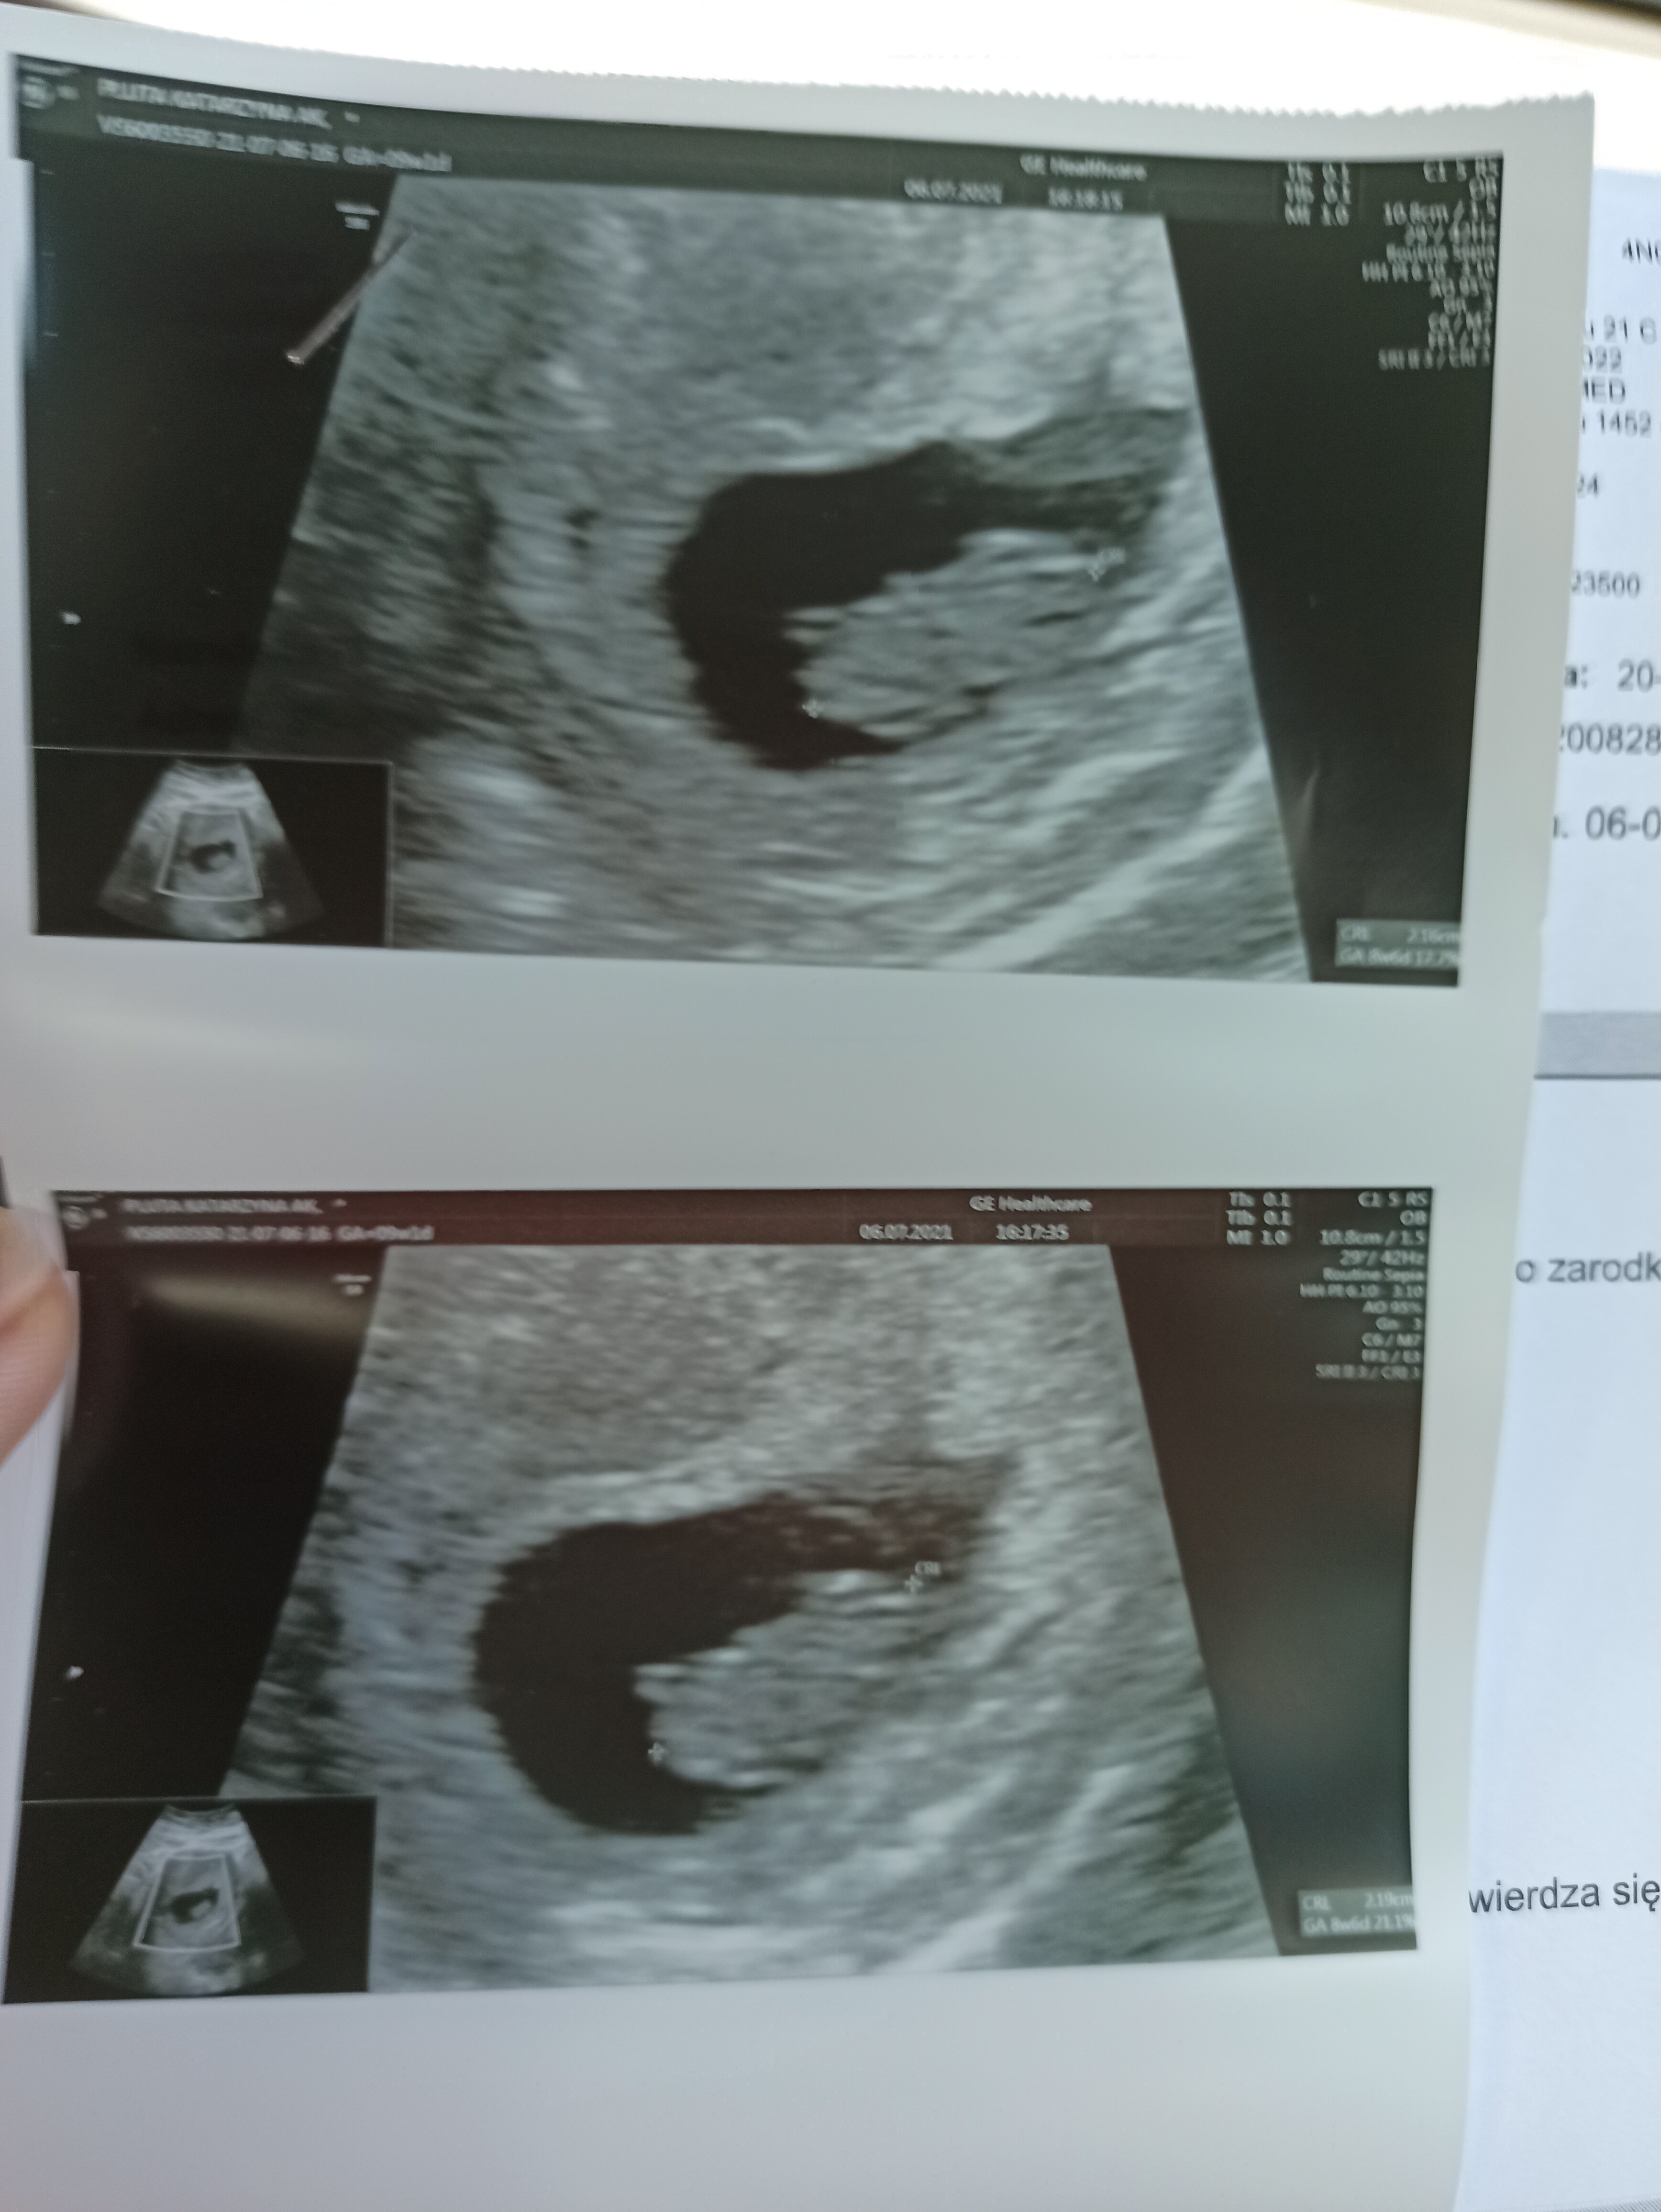

Ale duża Dzidzia 😍 To już nie taka "fasolka" a całkiem zacny miś Haribo! 💖💖💖💖 Wspaniale 😀 Ja też uwielbiam oglądać Wasze usg 😁 To takie niesamowite.

Jak najbardziej niedosyt… Byle do pon. 😁 i może ktoś jeszcze będzie miał ochotę wstawić zdj , super się ogląda zmianę od kropeczki do małego człowieczka 😊

Ja miałam do tej pory 2 USG na przestrzeni 2 tygodni - pierwsze prywatnie i było super widać pęcherzyk i zarodek obok, do tego dodatkowy ekran przede mną, żebym wszystko widziała. Drugie USG 8+6 w Luxmed, nie dość, że okropna baba, to jeszcze nie miałam nawet jak spojrzeć na ekran, trwało to chwilę i dostałam tylko wydruki - zdjęcia jak dla mnie przypomniały chomika, żadnych kształtów dziecka. Straszna jakość. Teraz na prenatalne też pójdę prywatnie, bo aż mi szkoda tamtej wizyty, Luxmed chyba nadaje się głównie do robienia badań z pakietu

• IMG_20210706_163527.jpg

IMG_20210706_163527.jpg

1,2 MB · Wyświetleń: 85